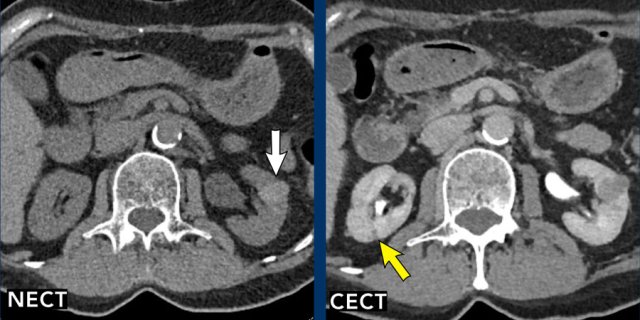

Images

Lesion 1 (yellow arrow)

A homogeneous, hypodense lesion is seen in the posterior right kidney. This lesion is too small to characterize and is classified as Bosniak II.

Lesion 2 (white arrow)

On the non-enhanced CT (NECT) there is a hyperdense lesion in the left kidney with HU > 70, which would normally correspond to a Bosniak II lesion (white arrow). A contrast-enhanced CT (CECT) in the portovenous phase shows no significant contrast uptake but there is an inhomogeneous appearance.

This requires additional imaging with MRI (see next images).